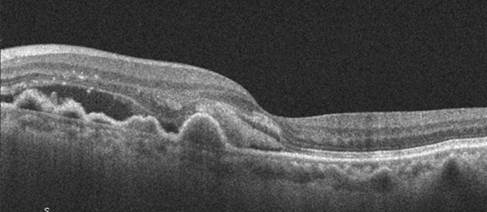

OCT macular

• Evaluación de presencia de drusas, alteraciones pigmentarias del EPR

• Detección de signos de neovascularización (exudados, hemorragias)

• Evaluación del EPR y extensión de la atrofia

• Comparación con exámenes previos para detectar progresión

• Forma Húmeda (Neovascular)

• Neovascularización coroidea (NVC) activa

• Exudación, hemorragias retinianas o subretinianas

• Desprendimiento del EPR o de la retina neurosensorial

• Progresión rápida en ausencia de tratamiento

• Pérdida visual central severa

• Metamorfopias y escotomas